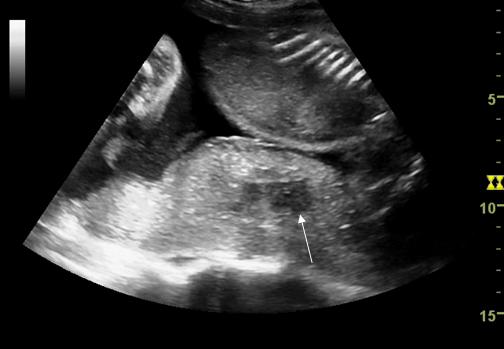

Fig. nr. 223. Hematom retroplacentar ( sageata )relativ recent, hipoecogen ,la o sarcina de 30 sapt. cu DPPNI.